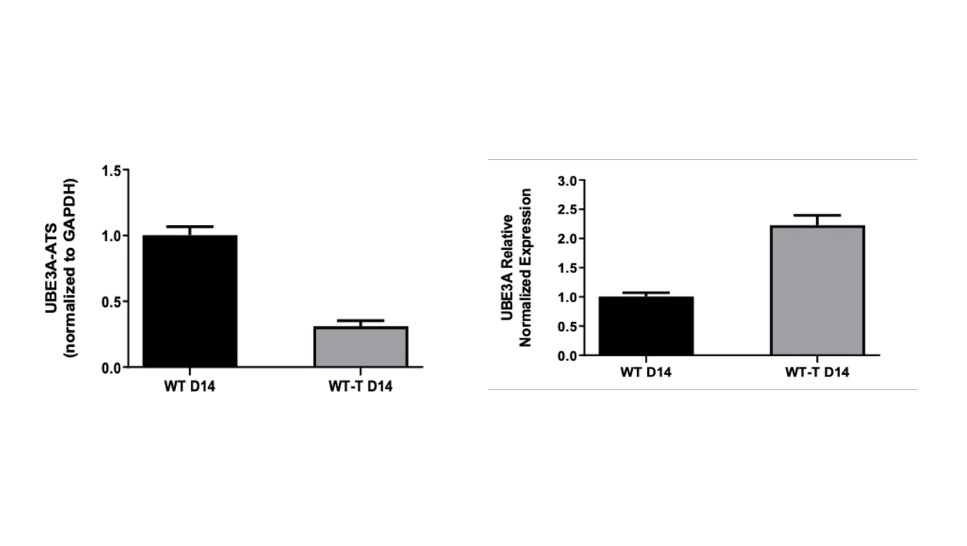

研究目标:利用 iPSC 衍生的皮层神经元评估靶向 UBE3A 的 ASO 的疗效。

ASO 治疗: 在第 14 天对神经元进行给药,并持续监测 9 天

基因表达分析: 通过 qPCR 检测到 UBE3A 表达上调,同时 UBE3A-ATS 表达下调

关键结果

结果证明了 ASO 在调节神经元模型中的靶基因方面的有效性,突显了其在神经治疗应用方面的潜力。